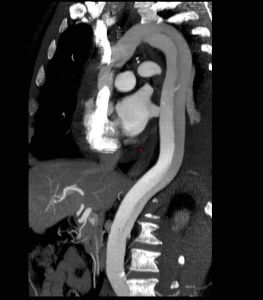

主動脈夾層動脈瘤(二)X線 胸部平片見上縱隔或主動脈弓影增大,主動脈外形不規則,有局部隆起。如見主動脈內膜鈣化影,可準確測量主動脈壁的厚度。正常在2~3mm,增到10mm時則提示夾層分離可能性,若超過10mm則可肯定為本病。主動脈造影可以顯示裂口的部位,明確分支和主動脈瓣受累情況,估測主動脈瓣關閉不全的嚴重程度。缺點是它屬於有創性檢查,術中有一定危險性。CT可顯示病變的主動脈擴張。發現主動脈內膜鈣化優於X線平片,如果鈣化內膜向中央移位則提示主動脈夾層,如向外圍移位提示單純主動脈瘤。此外CT還可顯示由於主動脈內膜撕裂所致內膜瓣,此瓣將主動脈夾層分為真腔和假腔。CT對降主動脈夾層分離準確性高,主動脈升、弓段由於動脈扭曲,可產生假陽性或假陰性。但CT對確定裂口部位及主動脈分支血管的情況有困難,且不能估測主動脈瓣關閉不全的存在。

(四)磁共振成像(MRI) MRI能直接顯示主動脈夾層的真假腔,清楚顯示內膜撕裂的位置和剝離的內膜片或血栓。能確定夾層的範圍和分型,以及與主動脈分支的關係。但其不足是費用高,不能直接檢測主動脈瓣關閉不全,不能用於裝有起搏器和帶有人工關節、鋼針等金屬物的病人。

(五)數字減影血管造影(DSA) 無創傷性DSA對B型主動脈夾層分離的診斷較準確,可發現夾層的位置及範圍,有時還可見撕裂的內膜片,但對A型病變診斷價值較小。DSA還能顯示主動脈的血流動力學和主要分支的灌注情況。易於發現血管造影不能檢測到的鈣化。